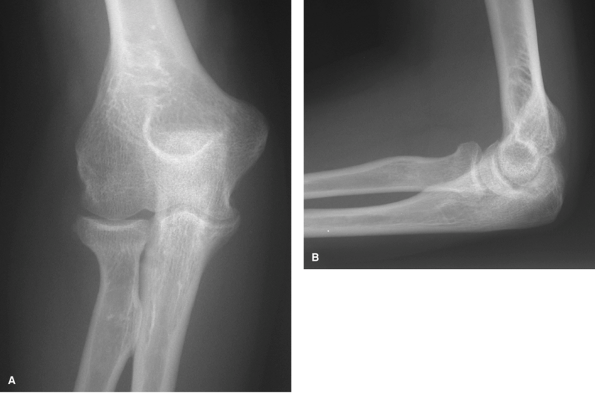

![]() |

Figure 62-2 A: Stage I rheumatoid arthritis. B: Stage I rheumatoid arthritis.